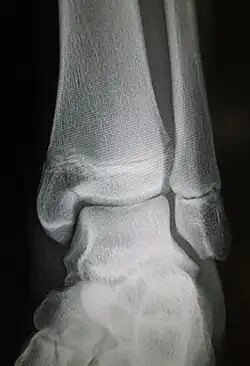

Maisonneuve fracture

| Radiograph showing a Maisonneuve fracture of the proximal fibula | |

The Maisonneuve fracture is a spiral fracture of the proximal third of the fibula associated with a tear of the distal tibiofibular syndesmosis and the interosseous membrane. There is an associated fracture of the medial malleolus or rupture of the deep deltoid ligament of the ankle. This type of injury can be difficult to detect.[1][2]

Ankle radiographs are used to detect widening of the tibiofibular syndesmosis or medial clear space. The medial clear space is the area between the talus of the ankle and the medial malleolus. Damage to the deltoid ligament and syndesmotic ligaments result in mortise instability, causing the talus to laterally shift and widen the medial clear space.[4][12] A clinical study, conducted in 2006 and published in the Journal of Bone and Joint Surgery, found that the medial clear space size of a normal ankle and an injured ankle measured at 4 millimetres and 5.4 millimetres in length respectively.[11] To confirm diagnosis, full-leg radiographs are used to inspect for fractures of the proximal fibula and widening of the interosseous clear space (or tibiofibular clear space). The interosseous clear space is the area between the medial side of the fibula and lateral side of the tibia. A peer-reviewed study, published in Injury in 2004, found that an interosseous clear space greater than 10 millimetres indicates diastasis of the syndesmotic ligaments.[4]